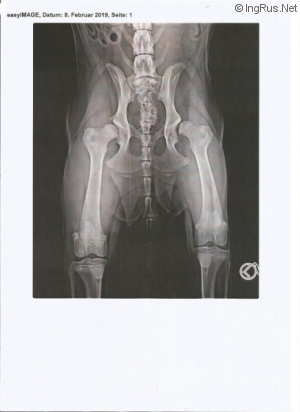

| Championship | most severe HD E/D not operable |

![]() ROSKOSH ALPIYSKIKH LUGOV GRETA GARBO 2018most severe HD E/D not operable |